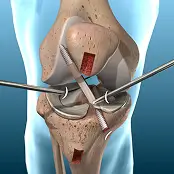

Knee Orthopedic Surgery